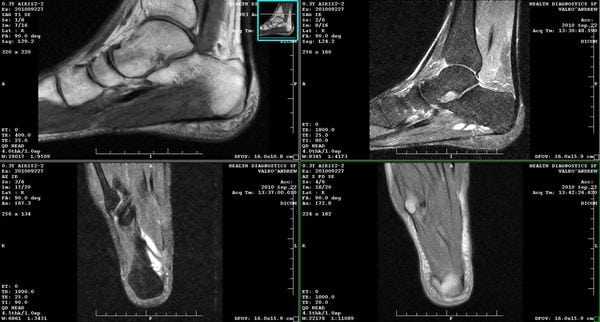

(Слева) МР-артрография в режиме Т1ВИ, коронарный срез, пациент 25 лет: визуализируется обширное повреждение суставного хряща подтаранного сустава вследствие перелома пяточной кости.

(Справа) МР-артрография в режиме Т1 ВИ, сагиттальный срез: спереди видны участки неизмененного хряща, а сзади - выраженное его истончение. В голеностопном суставе отмечаются признаки остеоартроза. У этого пациента подтаранный сустав сообщается с полостью голеностопного сустава. Лечение заключалось в артродезе обоих суставов.